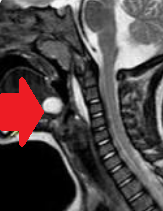

Thyroglossal duct cysts. Neck MRI – Detailed imaging of the cyst. Courtesy Dr. V. Penopoulos.